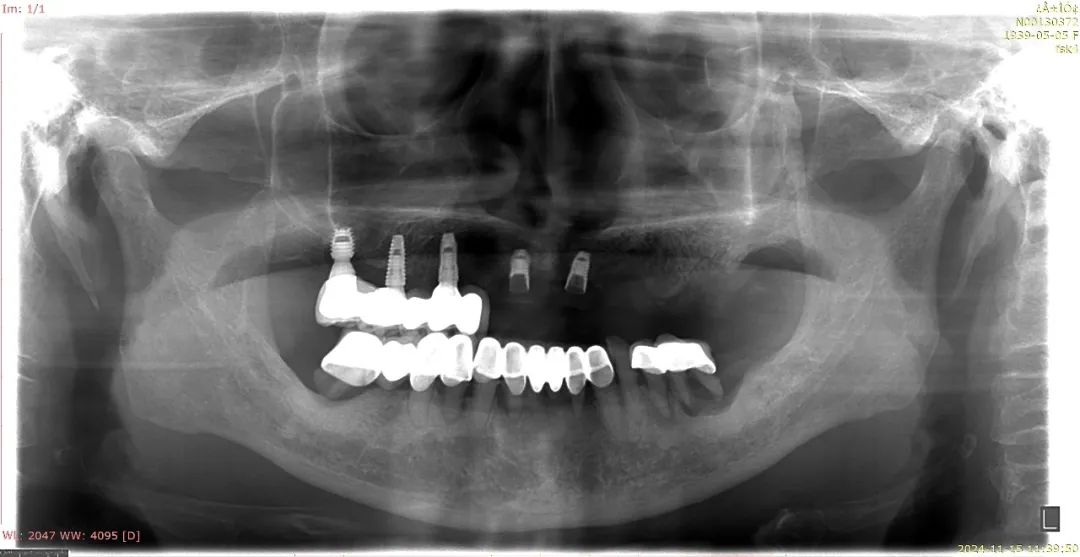

经检查发现,柯女士上颌中间的两枚种植体,其中一枚基台折断,螺丝也有部分折断在植体里,另一枚连部分植体都断裂了。医生告知,若想继续做种植牙,需要先剖开牙床取出两枚坏掉的种植体才行,这对一位高龄老人来说损伤太大。2024年11月,柯女士选择在口腔医院完成了几颗上颌牙的活动义齿修复。

柯女士的牙齿拍片显示,中间上颌牙种植的两枚种植体已有断裂。林先生 供图

口腔医院医生表示,柯女士其中一枚种植体基台折断,螺丝也有部分折断在植体里,另一枚连部分植体都断裂了。林先生 供图